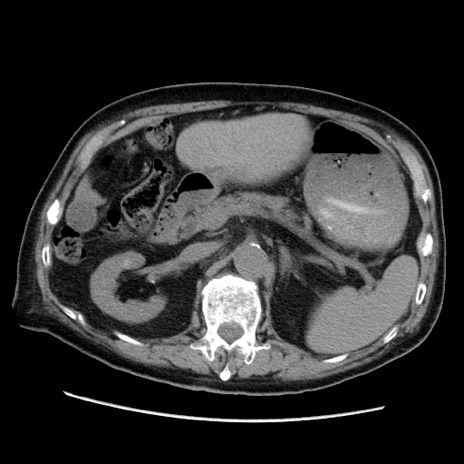

症例21(横断像)

【症例】70歳代男性

【主訴】腹痛

【現病歴】肝硬変・肝細胞癌にてかかりつけの方。約9時間前に食後より腹痛出現。症状が徐々に増悪し、嘔吐出現したため来院。

【既往歴】肝硬変、肝細胞癌(RFA、TACE後)

【身体所見】意識清明、表情苦悶様、BT 36℃、BP 129/78mmHg、P 88bpm、SpO2 97%(RA)、右上腹部から心窩部にかけて圧痛あり、反跳痛なし、筋性防御あり。

【データ】WBC 5800、CRP 0.16